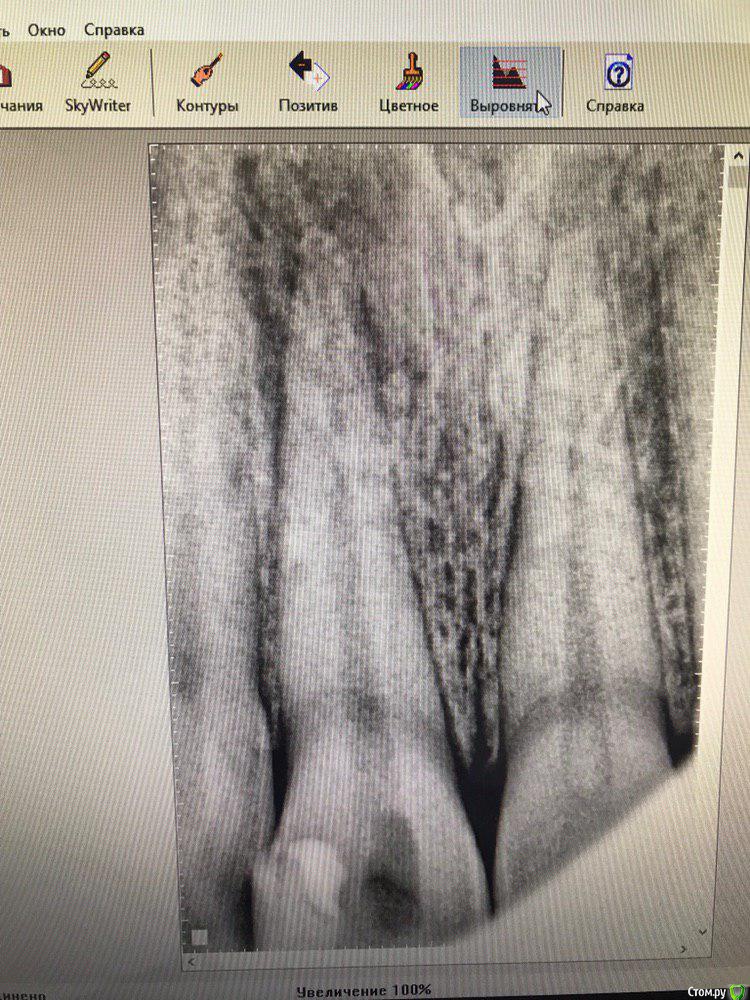

Mashaa1337 Опубликовано 31 августа, 2019 Автор Поделиться Опубликовано 31 августа, 2019 что скажете по поводу этого зуба? есть ли шансы на спасение? женщине 66 лет Ссылка на комментарий

vse32 Опубликовано 31 августа, 2019 Поделиться Опубликовано 31 августа, 2019 что скажете по поводу этого зуба? есть ли шансы на спасение? женщине 66 летНет Ссылка на комментарий